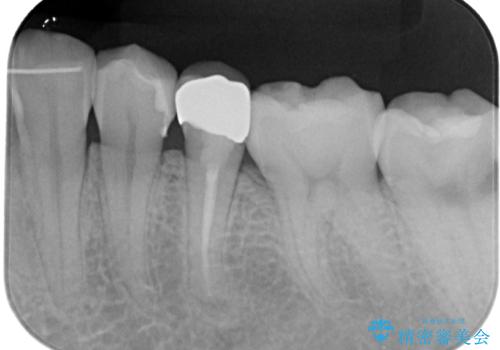

- 左下の被せものが割れたとのことで来院された患者様です。検査の結果、左下の前から4番目の歯はセラミックインレー修復、左下の5番目のところはオールセラミッククラウンによる補綴治療を行っていくことにしました。

拡大鏡視野下で被せもの、虫歯の除去を行い、オールセラミッククラウン、セラミックインレーに適した形に整えました。

歯と歯茎の間に圧排糸と言われる糸を入れてシリコーン印象材にて精密な型どりをしました。

セラミックインレーの装着時には、唾液の侵入を防ぐために、ラバーダム防湿を行いました。

適合の良い被せものが入り、審美面も気に入っていただけました。被せものが割れていたという経緯もあったため少しだけ被せものの厚みを多めに確保してあります。